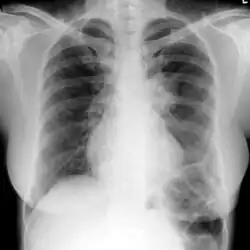

The extent of infection may be seen on X-ray or CT scan. On chest X-ray and CT, pulmonary aspergillosis classically manifests as a halo sign, and later, an air crescent sign.[21]

Chest X-ray: mass overlying the left hilum